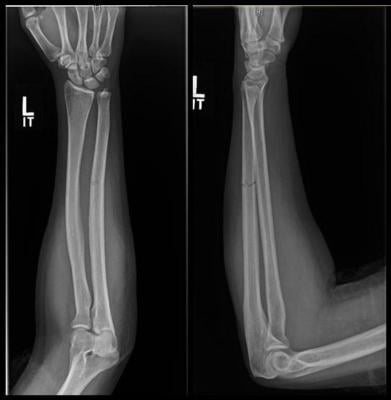

X-ray shows fracture to the ulna bone of the forearm. Image courtesy of RSNA

Fractures to the ulna, the bone on the pinkie side of the forearm, often occur when people hold up their hands to protect their faces from being struck with an object. These breaks are referred to as “nightstick fractures,” because they are frequently seen in people who try to block blows from nightsticks wielded by police officers.

Analysis of the radiographs demonstrated that intimate partner violence was strongly associated with minimally displaced fractures.

“The radiological characteristics we were looking at were the location of the fracture, the pattern of the fracture in terms of how it broke, and the displacement of the fracture,” said study lead author David Sing, M.D., an orthopedic surgery resident at Boston Medical Center. “Out of all those things, what we usually saw was a minimally displaced fracture, meaning the bone is broken all the way through but has not shifted significantly.”